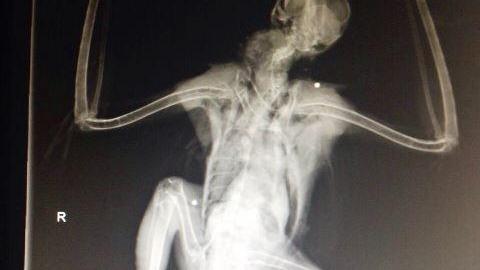

Un esemplare di Poiana-Buteo buteo ferito da colpi di fucile

"Ennesimo criminale atto di bracconaggio". Così il presidente della Lipu Ferrara Borghi commenta quanto accaduto a Porto Tolle, dove un esemplare di poiana è stato colpito da diverse pallottole. L'animale è stato portato dall’Assoc. Lida, al Centro di Recupero della Lipu Giardino delle Capinere a Ferrara, in un primo momento era stato consegnato alla Forestale di Bosco Mesola, da un signore che l’aveva raccolto nella zona di Porto Tolle (RO), dopo aver visto delle persone sparargli. Il fatto è stato confermato dalle radiografie effettuate dal Dr. Caldarelli, che evidenziano la presenza di pallini di piombo in vari punti del corpo, ed ha effettuato un primo intervento per la riduzione della frattura sulla zampa destra, sperando che non siano state colpite parti interne su cui è molto più difficile intervenire. "E' senza alcun dubbio un atto vandalico consapevole, in quanto è impossibile anche per il più sprovveduto delle persone che girano con un fucile, confonderla con una specie cacciabile".